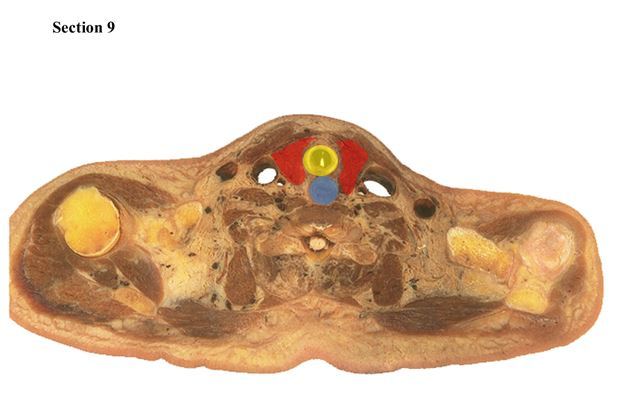

9

The yellow organs are the _____

The red structure is the _____

The blue structure is the _____

A

lungs

trachea

esophagus